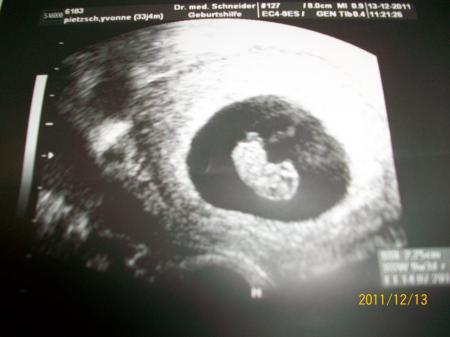

Hallo Limkisa.Das hab ich vor ein paar Wochen auch so ähnlich mit meinen Freund bzw.Ex gemacht.Ich habe wegen ihm auch die Pille abgesetzt weil er Kinder haben wollte ,und dann bin ich schwanger geworden ,und das Ende vom Lied war ,das er mich verlassen hat.Weil er dann aufeinmal der Meinung war das es jetzt nicht passe würde ,somit hat er mich vor die Wahl gestellt entweder ich treibe ab oder er verlässt mich wenn ich es nicht tun würde.Ich habe mich gegen eineAbtreibung entschieden ,ich bin doch nicht blöd.Ich bekomme das baby auch ohne ihn groß. fühl dich mal gedrückt. lg Yvonne und so sieht mein Baby jetzt aus

Bild zu